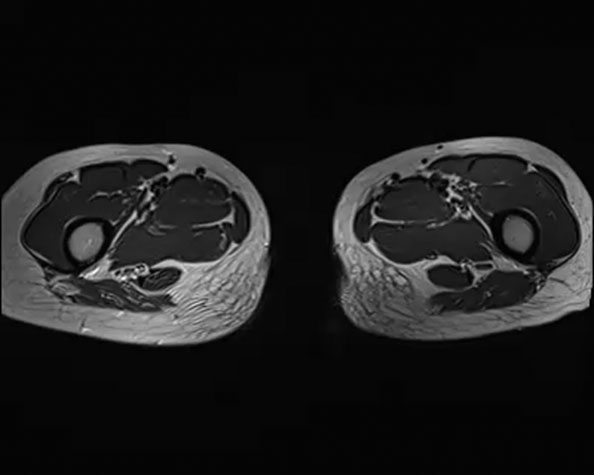

Ameliyat öncesi: MR’da lomber 4.vertebradan başlayıp sakrum ve iliak kanattan kalça eklemine kadar uzanan yumuşak dokuyu infiltre eden ve kemik harabiyetine neden olan tümör dokusu görülmekte